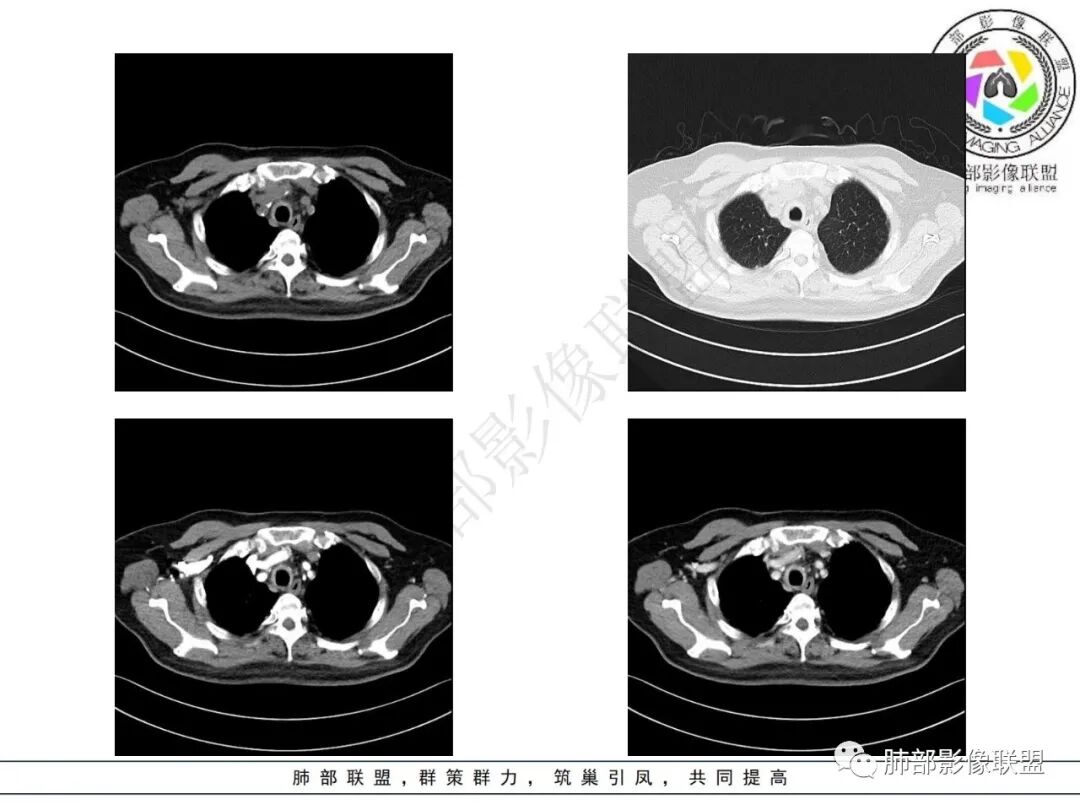

老年男性,气管入口至右主支气管壁弥漫性增厚,累及膜部,未见结节状凸起,考虑气管支气管淀粉样变性,鉴别复发性多软骨炎(不累及膜部),弥漫肉芽肿多血管炎(结节状增厚)。

老年男性,气管全层受累(膜部受累),累及气管、主支气管,纵隔、肺门区无肿大淋巴结,首先考虑淀粉样变性,没有结节感,不考虑TO,复发软骨炎不累及膜部

老年男性,气管支气管壁广泛增厚、钙化,膜部受累轻,增强轻中度强化,定位气管支气管软骨部病变,考虑复发性多软骨炎,鉴别淀粉样变性,排除韦格、骨化性气管支气管病、结节病、结核、真菌等

患者,男,73,间断咳嗽半年,加重半月。双肺底细湿啰音,双下肢轻度水肿。糖尿病、糖尿病微血管病变、慢性肾病、高血压、冠心病、陈旧心梗、冠脉支架、脑梗、慢性胃病史,得全了。吸烟史。血像、ESR增高。胸部CT:气管壁弥漫全层增厚,膜部也受累,气管腔外形仍在、无缩窄,病变延及左右主支气管,纵隔可见肿大淋巴结,大血管壁多发钙化,双肺上叶可见多发树芽,两侧胸膜局限性增厚。考虑:TB?淀粉样变?鉴别GPA、复发性多软骨炎、气管支气管骨化、转移性钙化等。